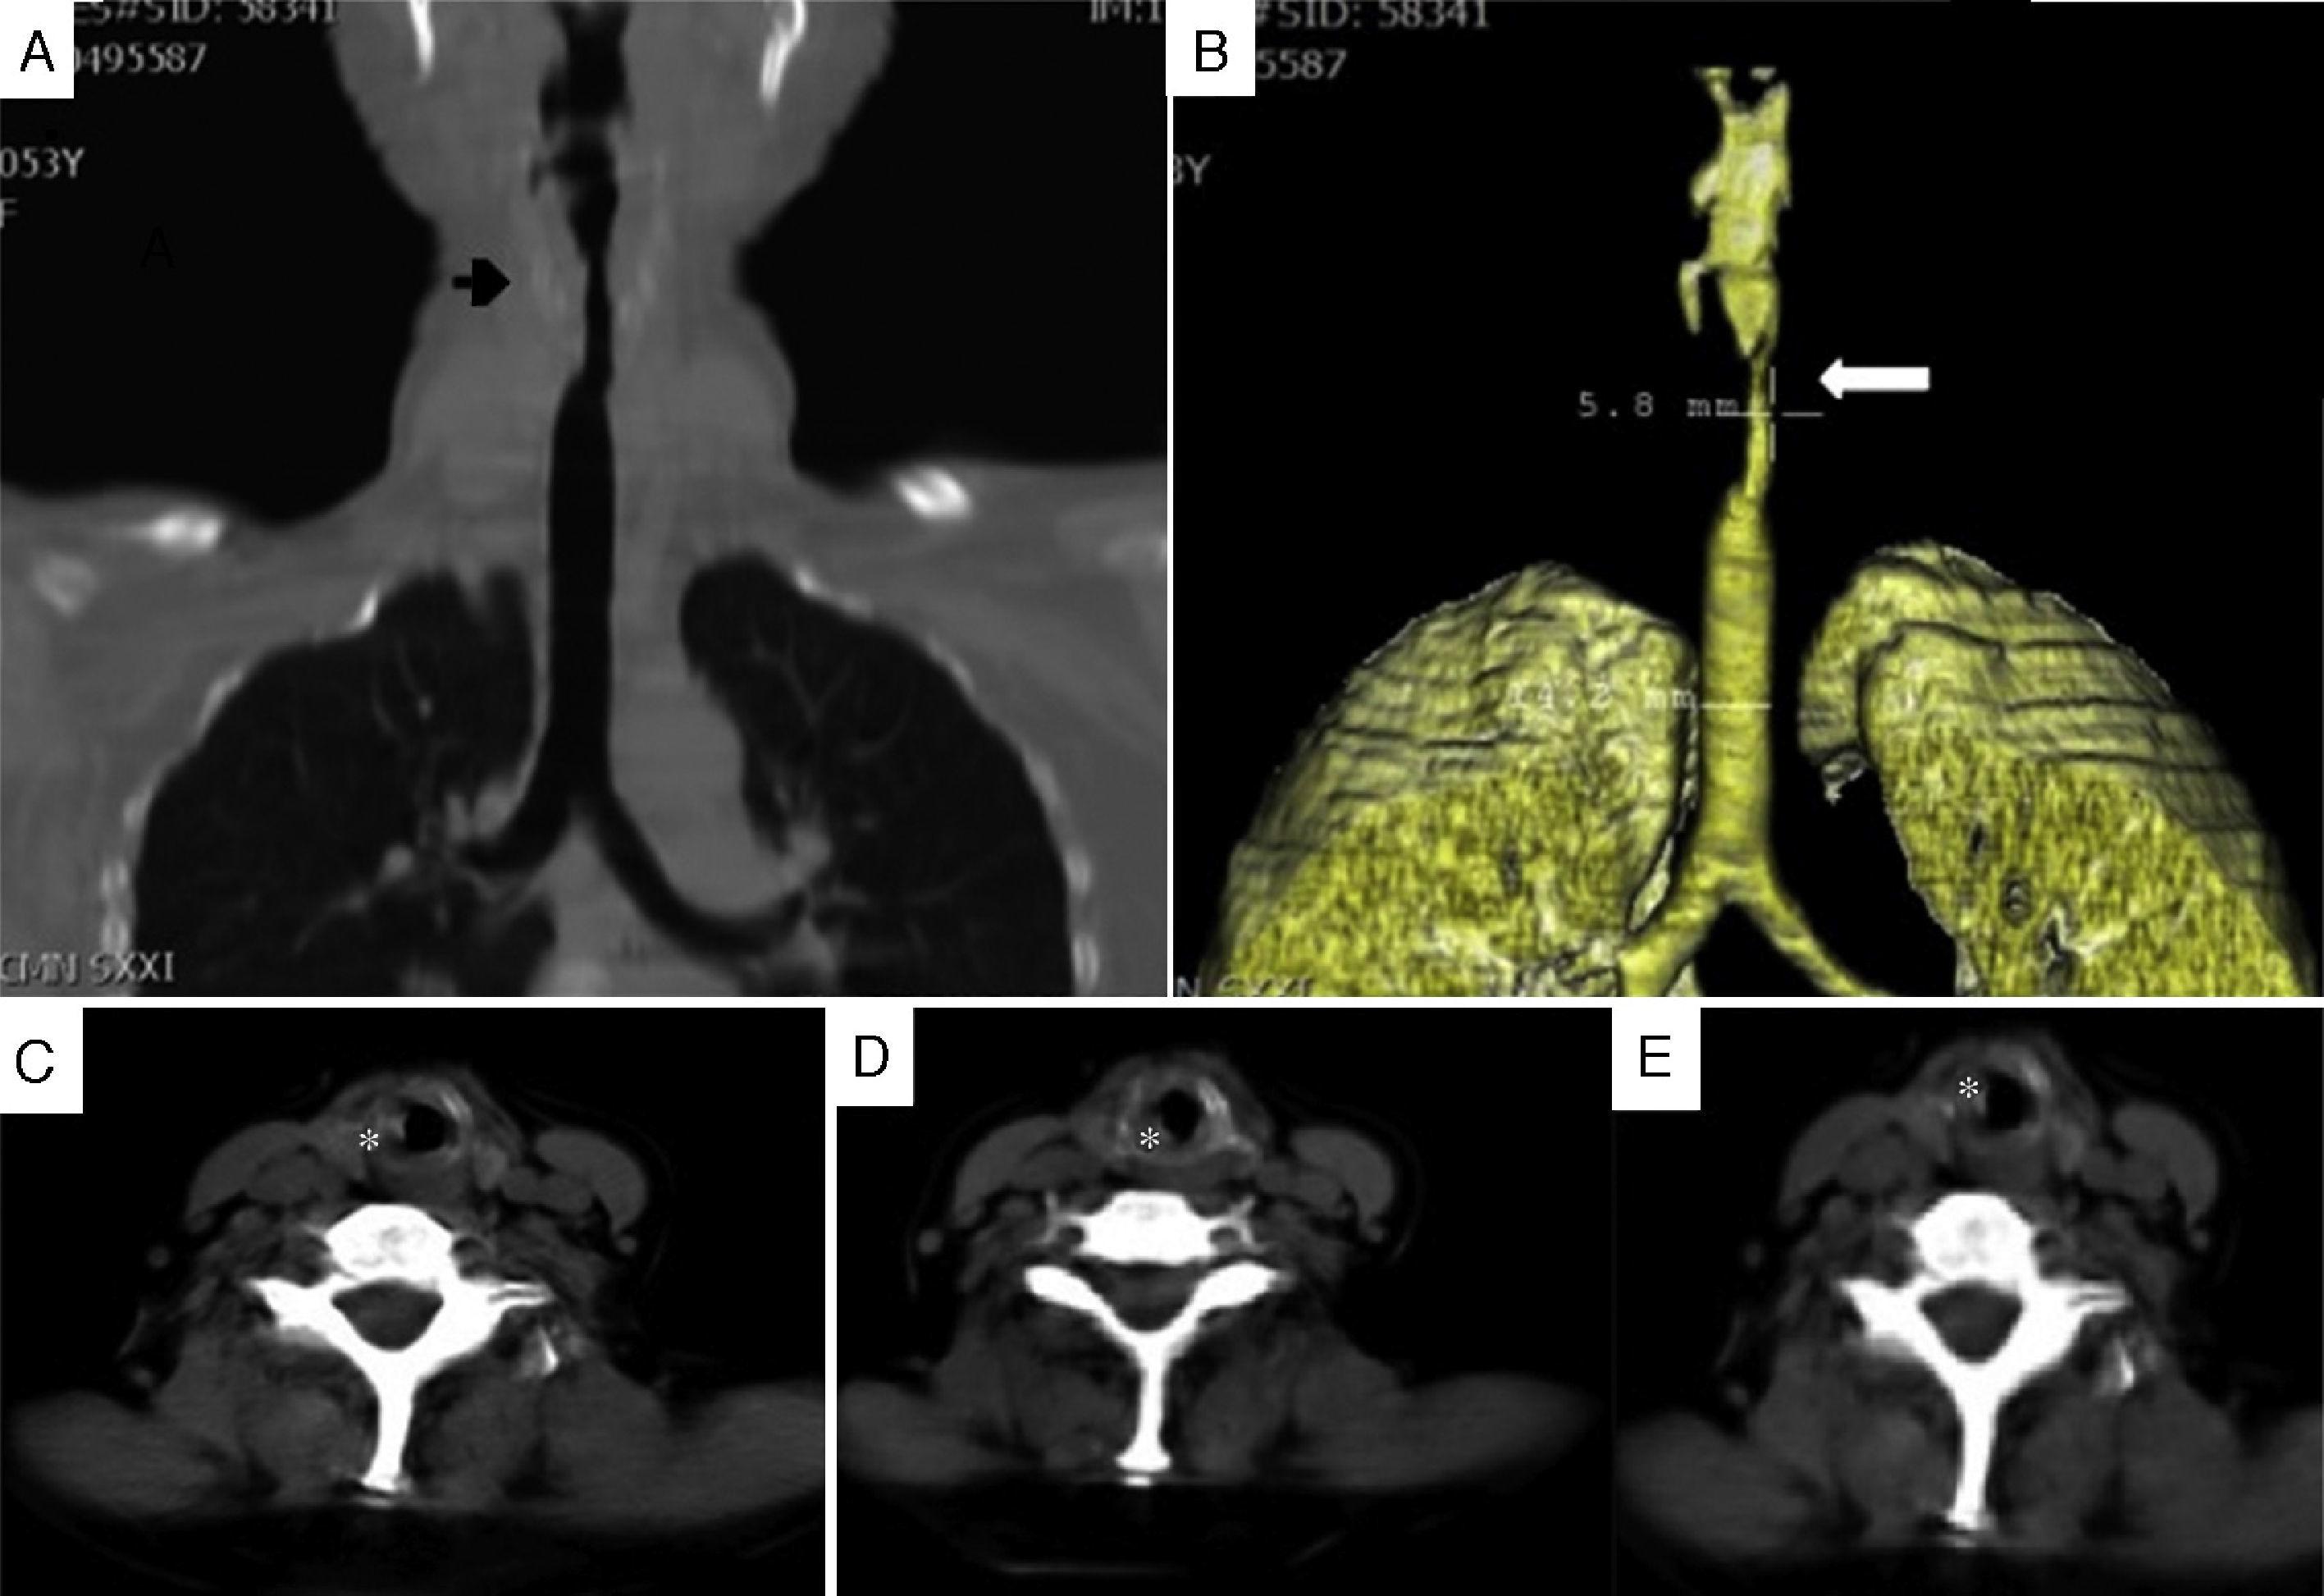

From www.semanticscholar.org

Figure 1 from Laryngotracheobronchial amyloidosis presenting severe Laryngostenosis In A Sentence laryngeal stenosis is a congenital or acquired narrowing of the airway that may affect the supraglottis,. otolaryngologist alexander hillel, m.d., director of the johns hopkins complex airway clinic, discusses complex airway. Abnormal narrowing of the larynx. laryngotracheal stenosis (lts) is a life threatening, fixed, extrathoracic restriction. the larynx is a structure made up of cartilage, muscle. Laryngostenosis In A Sentence.

Figure 2 from Laryngotracheobronchial amyloidosis presenting severe Laryngostenosis In A Sentence laryngeal stenosis is a congenital or acquired narrowing of the airway that may affect the supraglottis,. laryngotracheal stenosis (lts) is a life threatening, fixed, extrathoracic restriction. See ‘meaning & use’ for definition, usage, and quotation evidence. the larynx is a structure made up of cartilage, muscle and other soft tissues that sits above the windpipe and plays. Laryngostenosis In A Sentence.